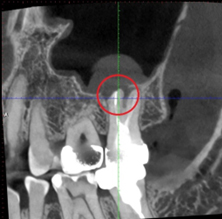

我們先收集術前X光片與電腦斷層,以利黃醫師評估診斷。經由X光片可發現該顆牙齒根管以於多年前治療過,並且製作了假牙配戴。另從電腦斷層上也發現根尖部分有發炎反應。

(術前CT)

術後經過兩個月的追蹤,從電腦斷層與X光片來看,根尖的發炎反應與治療前相比,黑影有明顯變小許多,患者也表示治療完後牙齦腫脹的感覺有逐漸改善,對於結果非常滿意,也十分感謝黃醫師的幫助與努力。